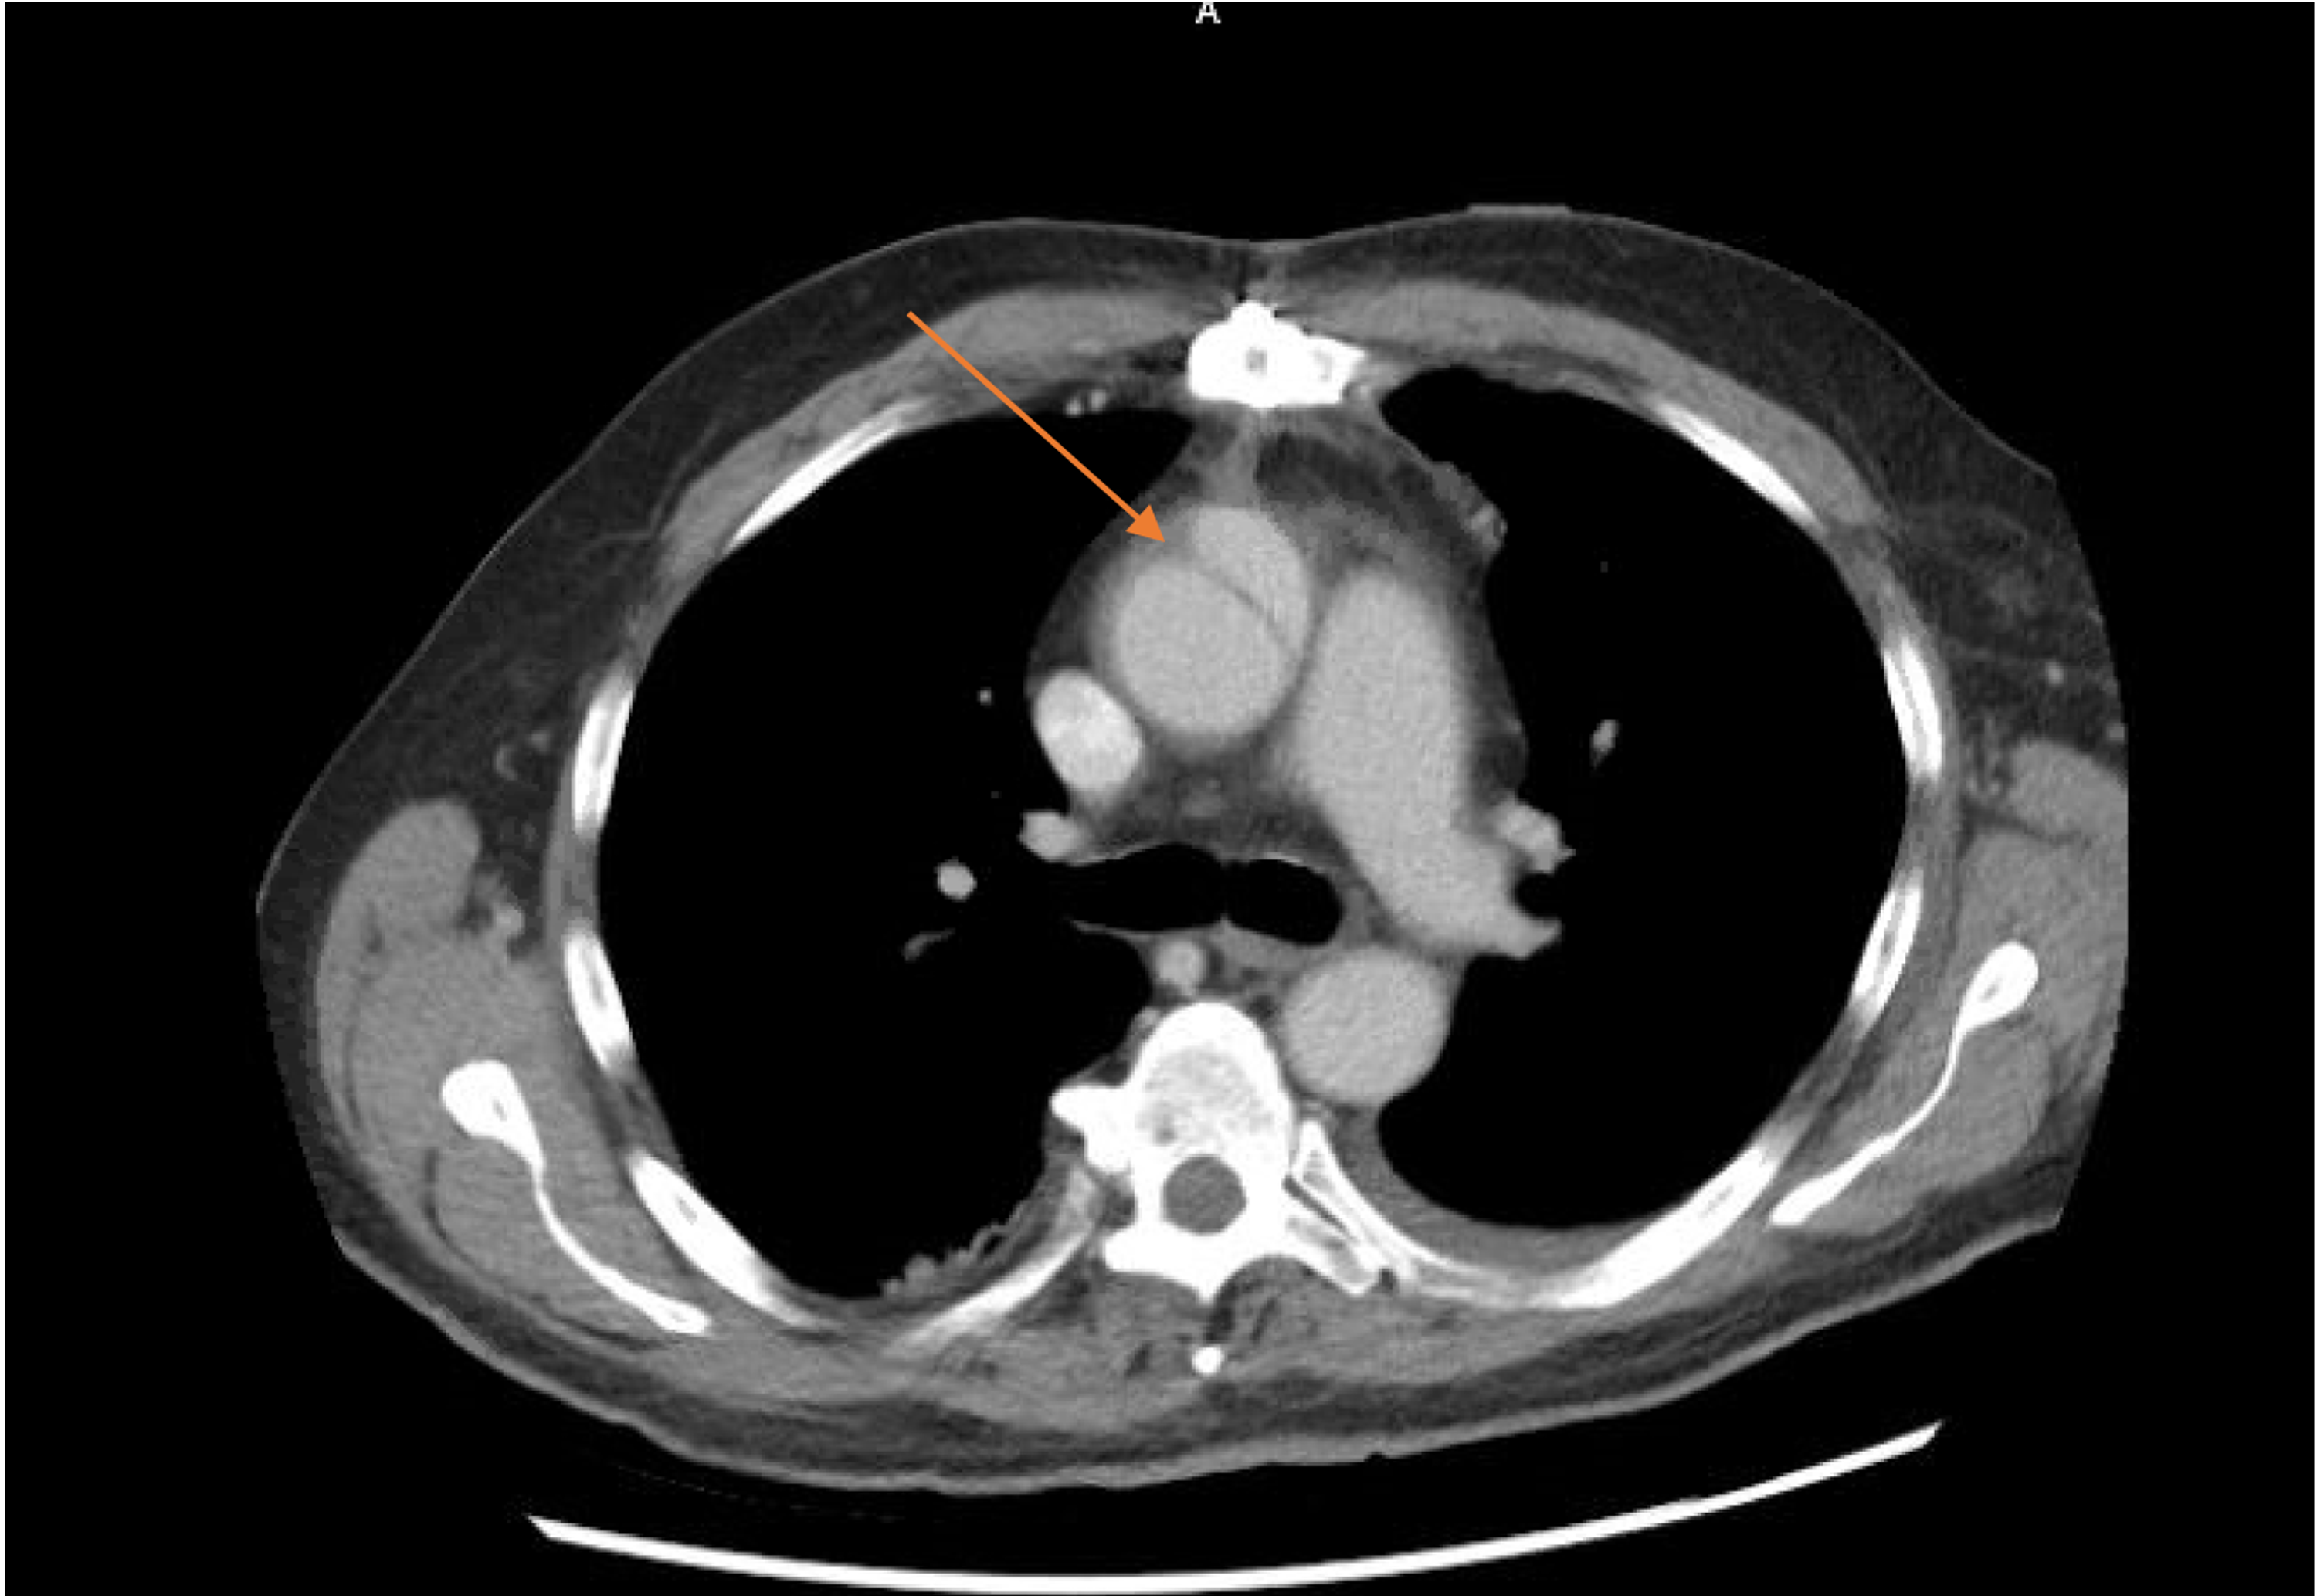

Dilated Ascending Aorta Chest Case Studies CTisus CT Scanning Ct Anatomy Of Ascending Aorta Nowadays, ct represents the most widely employed technique for the study of the thoracic aorta. Pulsation artifact particularly affects evaluation of the aortic root and ascending aorta. Pathology in adults, an ascending aortic diameter greater than 4 cm is. Normal anatomy of the thoracic and abdominal aorta. Dilatation of the ascending aorta is a common finding in the elderly but. Ct Anatomy Of Ascending Aorta.

Ascending Aortic Aneurysm on CT Scans Stock Photo Image of blood Ct Anatomy Of Ascending Aorta Pathology in adults, an ascending aortic diameter greater than 4 cm is. Nowadays, ct represents the most widely employed technique for the study of the thoracic aorta. Normal anatomy of the thoracic and abdominal aorta. Landmarks of ascending aortic anatomy. Dilatation of the ascending aorta is a common finding in the elderly but unusual in younger patients. An image showing. Ct Anatomy Of Ascending Aorta.

CT and MRI Assessment of the Aortic Root and Ascending Aorta AJR Ct Anatomy Of Ascending Aorta Pulsation artifact particularly affects evaluation of the aortic root and ascending aorta. Landmarks of ascending aortic anatomy. Nowadays, ct represents the most widely employed technique for the study of the thoracic aorta. Normal anatomy of the thoracic and abdominal aorta. Pathology in adults, an ascending aortic diameter greater than 4 cm is. An image showing normal aortic root and ascending. Ct Anatomy Of Ascending Aorta.

CT and MRI Assessment of the Aortic Root and Ascending Aorta AJR Ct Anatomy Of Ascending Aorta Pathology in adults, an ascending aortic diameter greater than 4 cm is. Landmarks of ascending aortic anatomy. Landmarks of ascending aortic anatomy. Normal anatomy of the thoracic and abdominal aorta. Dilatation of the ascending aorta is a common finding in the elderly but unusual in younger patients. Nowadays, ct represents the most widely employed technique for the study of the. Ct Anatomy Of Ascending Aorta.